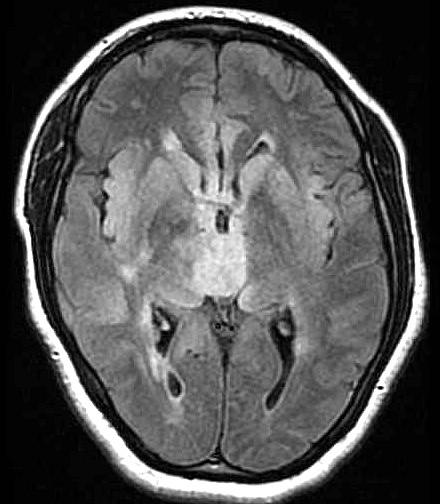

| Fem. 17a. |

| Nódulo sólido homogêneo preenchendo o III ventrículo, com limites precisos, com hipossinal em T1 e hipersinal em T2 e FLAIR, que se impregna por contraste paramagnético. Lesão menor implantada no assoalho do IV ventrículo provavelmente representa disseminação por via liquórica. |

| F. 17a. Tumor teratóide rabdóide atípico de III ventrículo. RM | HE | VIM, GFAP | HHF35, desmina, 1A4 | AE1AE3, EMA |